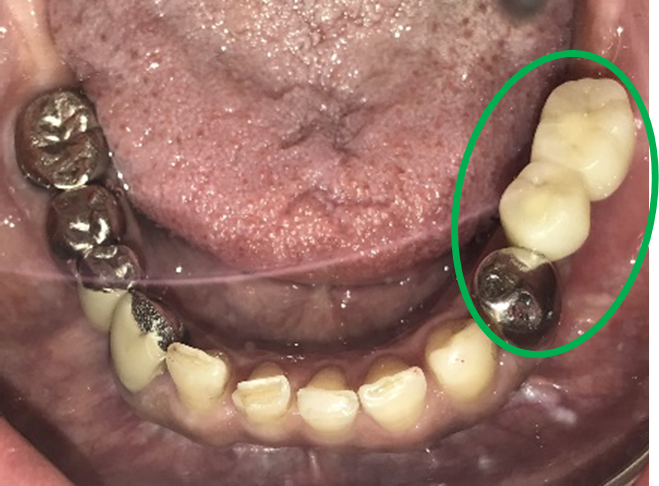

女性Mさん 40代(インプラント)

下、左右歯がないところに歯を入れたい。

治療内容

右下に2本、左下に1本インプラントを入れました。

所感

下顎左右奥の歯がないところに、インプラント治療を希望されて来院されました。X-Guideを使用し埋入しました。治療後「左右の奥歯でしっかり噛めてうれしいです。」と、とても喜んでくださいました。

インプラント3本:¥363,000×3本=¥1,089,000(税込)

Before

After